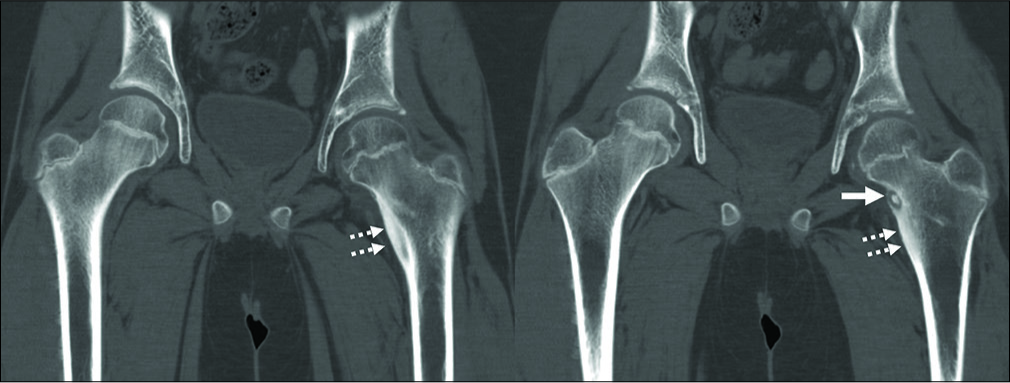

Slipped Capital Femoral Epiphysis (SCFE)